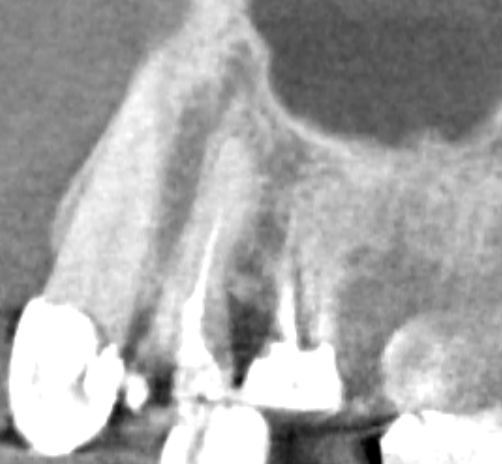

Sergey32132 Опубликовано 28 ноября, 2025 Поделиться Опубликовано 28 ноября, 2025 (изменено) Добрый день. Подскажите пожалуйста, в прошлую пятницу ел арахис, аккуратно, с моими зубами противопоказано, как то чувствую что один твердый и я почувствовал несильную боль в области 1,4, и вот по сей день болит десна на протяжении с 1,4 и до 1,6 включительно, и немного напухшая, но не флюс, в области стыка зуб\десна тоже если трогать или давить пальцем воспалена, а вот в области 1,4 еще продолжаются ноющие ощущения, где то глубоко аж там в области верхушки, если давить на него не болит, стучать инструментом тоже не болит. Открыл послднее кт трех недельной давности, там где смотрели что другие зубы и далее заживают после эндо лечения, посмотрел на эти, вроде воспаления нет, но обратил внимание что на 1,4 каналы не доплобированы до верхушек, по памяти, они были запломбированы лет 12 назад, и никогда этот зуб не беспокоил Вот сегодня иду к стоматологу там где микроскоп, реставрацию все равно планово нужно делать, потихоньку занимаюсь зубами, но как быть с 1,4, с одной стороны нужно было бы пролечить 1,4 раз не до конца. с другой стороны каналы таковы уже более 10 лет, и вряд ли имеет отношение к моей проблема то что я прикусил твердое. 3 дня назад делал обычный снимок. уже после как прикусил. Подскажите пожалуйста, как быть, и какова тактика, это скорее травматический периодонтит ? Перед этим один из стоматологов сказал что если была бы трещина, зуб реагировал бы если по нем стучать или кусать и сильно Изменено 28 ноября, 2025 пользователем Sergey32132 Ссылка на комментарий

Sergey32132 Опубликовано 28 ноября, 2025 Автор Поделиться Опубликовано 28 ноября, 2025 (изменено) апдейт: Сегодня пошел таки решил перелечить, правда врач с клиники где мне прошлые разы спасали не спасаемое, позвонили сказали что заболел, смог попасть в другую, здесь я первый раз, но тоже выбирал где есть микроскоп и работают с ним, трещины сегодня сказали не увидели, сегодня каналы а следующий раз реставрацию, но я сфоткал для себя снимок, и когда вышел уже обратил внимание на ход гуттаперчи в бок, подскажите пожалуйста, это судя по всему перфорация ? Если да, во всех ли случаях плохой прогноз ? Изменено 28 ноября, 2025 пользователем Sergey32132 Ссылка на комментарий